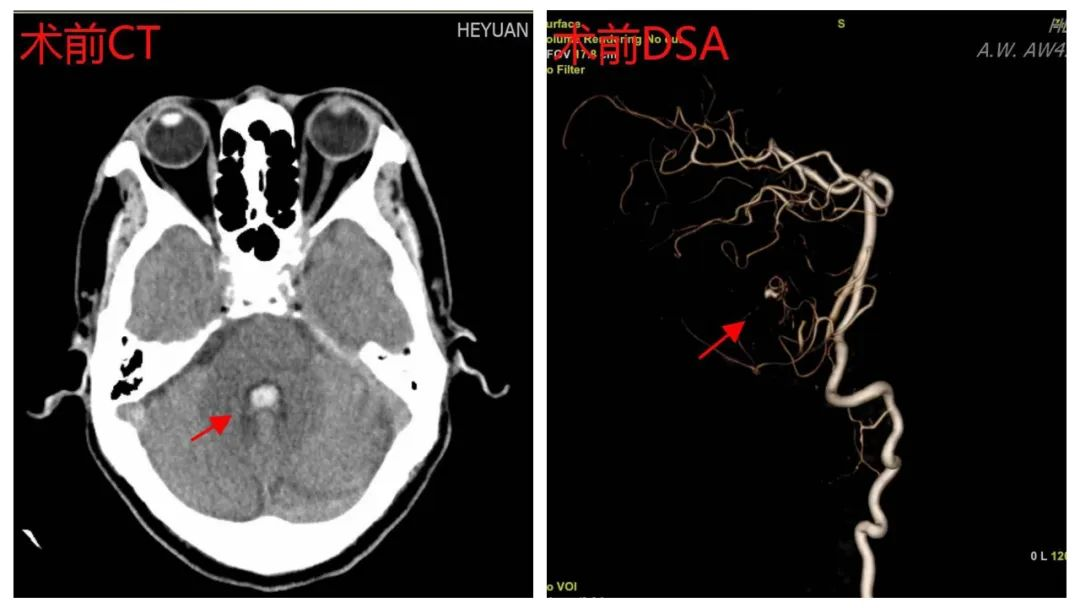

患者男性,65岁,因“头晕、头痛16小时”入院,入院CT提示小脑出血,进一步完善颅脑CTA及颅脑3.0T核磁共振后,考虑诊断小脑蚓部动静脉畸形出血,进一步全脑血管造影后,确诊为小脑蚓部动静脉畸形(b-AVMs)合并动静脉瘘(AVF),病变位于后颅窝,位置深,靠近脑重要结构(脑干),脑血管病变复杂,颈部血管、供血动脉迂曲,供血动脉细小;且患者经济贫困,未购买任何医疗保险。患者病情危重,病变部位随时可能再出血,危及生命安全,需尽快手术治疗。经科内讨论,并将患者情况向我科客座教授、广东省人民医院知名神经外科专家陈光忠主任医师汇报后,陈光忠教授指示:开颅手术创面大、损伤多,老年患者易发生并发症,且住院时间长,治疗费高;神经介入治疗创伤、负损伤小,住院时间短,费用少,建议采取介入治疗。

术前CT及DSA影像资料(箭头所指为病灶)